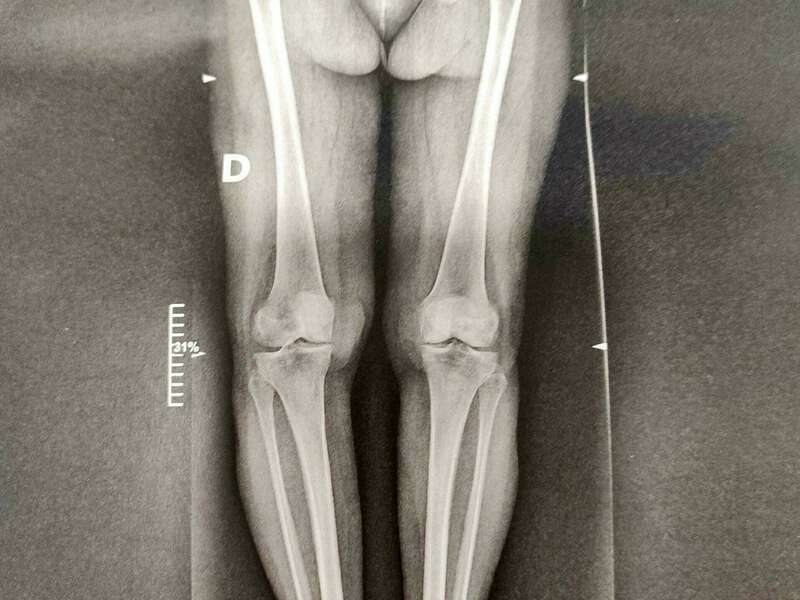

- Les anomalies anatomiques plus ou moins constitutionnelles : inégalité de longueur de membre, dysplasie fémoro-acétabulaire, luxation de hanche, les fracture de hanche, les lésions ligamentaires.

Elle sera confirmée par des examens radiologiques tels que des radiographies de hanche. En cas de doute diagnostic, afin d’éliminer un éventuel diagnostic différentiel, un scanner et/ou une IRM pourront être prescrits.